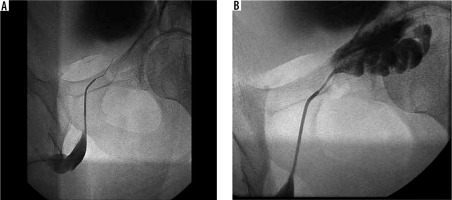

A 28-year-old man, surgically treated 2 years previously for clinical grade III bilateral varicocele (according to Dubin’s classification) who had not conceived for 16 months despite regular and unprotected sexual intercourse, was admitted to the Urology Department for suspected accidental surgical ligation of the left vas deferens. The spermiogram exhibited showed moderate oligospermia (7 million/ml) without evidence of teratospermia and asthenospermia. The hormonal dosage of FSH, LH, GnRH, prolactin, and total and free testosterone was normal. Liver, kidney, cardiological, and blood count tests were negative. The physical examination showed didymes and epididymes in place, not painful, and mobile. US confirmed the regular volume and echostructure of didymes and epididymis. Scrotal tunics were not thickened. There was no hydrocele. The proximal deferens bilaterally were not delated. In colour Doppler, the intratesticular vascularization was regular. Pathological reflux was not observed after Valsalva test in the anterior pampiniform plexus bilaterally although residual ectasia of the venous calibre (d.a.p. max 3 mm) was found especially on the left. In agreement with the urologist, we decided to perform a phlebography of the left pampiniform plexus, which confirmed the presence of the residual venous ectasia. Subsequently, bilateral vesico-deferentography was performed, which showed regular diameter, course, and patency of the vas deferens. The seminal vesicles were highly dilated, especially on the left due to steno-occlusion of the ejaculatory ducts; therefore, H2O gas insufflation was carried out with modest results, and the treatment was rescheduled. After 45 days, the patient exhibited a spermiogram, which showed severe oligospermia (1.5 million/ml) without alterations in the shape and motility of the spermatozoa. In agreement with the urologist, we decided to perform a combined treatment. Preliminarily, urethroscopy was performed, thus identifying the verumontanum and then selectively catheterizing the ejaculatory ducts through micro-catheter and H2O insufflation was performed with complete unblocking of the orifices. The spermiogram performed at 90 days was negative with a sperm count of 50 million/ml. Currently the patient is in excellent clinical condition and undergoes ultrasound control and annual spermiogram.

Imaging helps to identify the cause of infertility and classify it as obstructive or non-obstructive [9]. The imaging modalities routinely used to evaluate the reproductive system in males include ultrasound (US), magnetic resonance imaging (MRI), and interventional techniques such as venography and vesico-deferentography [10,11]. The scrotal ultrasound examination is the first level investigation [12,13]. It is performed using a high-frequency linear transducer with the patient in the supine position. The examination allows the evaluation of the echostructure and the volume of the testes (normal value: 9-12.5 cc), the peri-testicular structures, and the proximal tract of the deferens [1-14]. Colour Doppler also allows the study of intra-testicular vascular flow and the study of reflux after Valsava test of the pampiniform plexus. Trans-rectal ultrasound (TRUS) allows the study of the distal genital tract, including the distal vas deferens, seminal vesicles (normal value d.a.p.: 8-15 mm), prostate, and ejaculatory ducts (normal value: 10-22 mm) [15,16]. The CEUS allows the contrast study in cases of testicular and para-testicular incidental nodules [17]. MRI has excellent resolution of contrast and allows multiplanar reconstructions. It provides information on the entire male reproductive tract including the prostate, seminal vesicles, and ejaculatory ducts. Although it is considered an alternative to invasive radiology procedures [18,19], vesiculo-deferentography is the gold standard in the study of the deferens, seminal vesicles, and ejaculatory ducts. The procedure consists of an ultrasound-guided puncture of the vas deferens, subsequent injection of contrast under X-ray scanning, and filling of the ducts until it leaks into the bladder, confirming its patency, calibre, and course [20,21]. Treatment of obstructive azoospermia is usually surgical and involves the recovery of sperm through TESE and microTESE techniques. The advantages of interventional vascular radiology that allows minimally invasive treatments of the genitourinary system are described in the literature [22,23]; it allows the diagnosis and treatment of varicocele by endovascular scleroembolization [24]. However, there are no papers in the literature describing the treatment of obstructive oligozoospermia.

In our case, vesico-deferentography allowed a precise diagnosis of the stenosis point; the subsequent transurethral deferentography ensured the innovative minimally invasive treatment of the obstructive problem with an excellent final result and complete resolution of the oligospermia. Our experience suggests the great potential of radiological interventional treatment in steno-obstructive pathologies of the vesico-deferential system; however, it is essential to increase the number of cases treated.